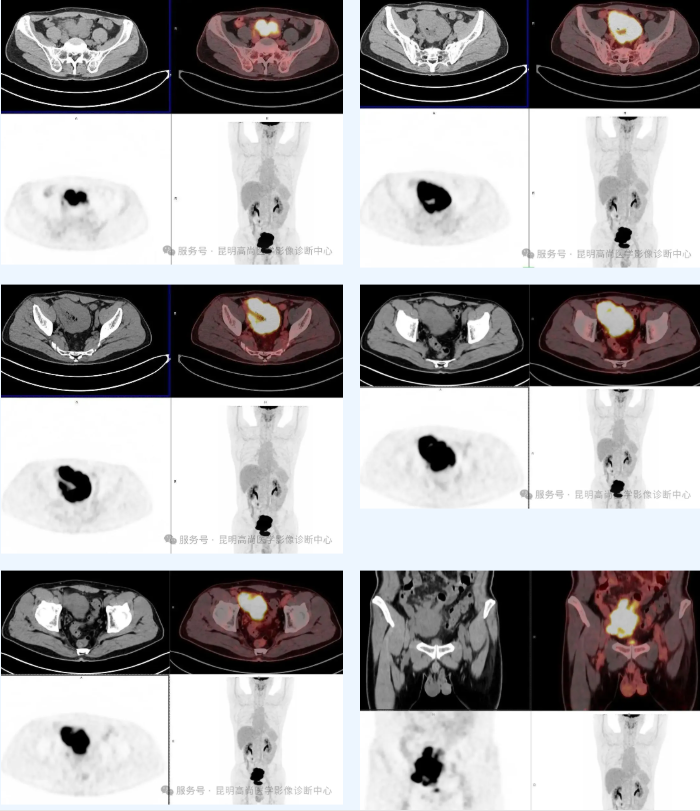

患者男性,51 岁;两个月前出现便血,外院胃肠镜:食道隆起病变,回盲部占位并狭窄;回盲部组织病检:恶性肿瘤,建议结合免疫组化;肿标 TSGF 偏高,要求 PET/CT 明确病变性质;既往右腕关节骨折史,痔疮手术史,否认外伤过敏史,否认传染病史。

盆腔内回肠巨大肿块并糖代谢明显增高,符合淋巴瘤;周围肠系膜多发淋巴结增大并糖代谢轻度增高,肿瘤浸润待排,建议随诊。

PET/CT:病变区域(如肠壁增厚处、肿块或受累淋巴结)通常会出现 FDG 摄取增高;治疗完成后,PET-CT 在检测残留或复发的淋巴瘤方面具有很高的敏感性,即使在早期阶段也能检测到。